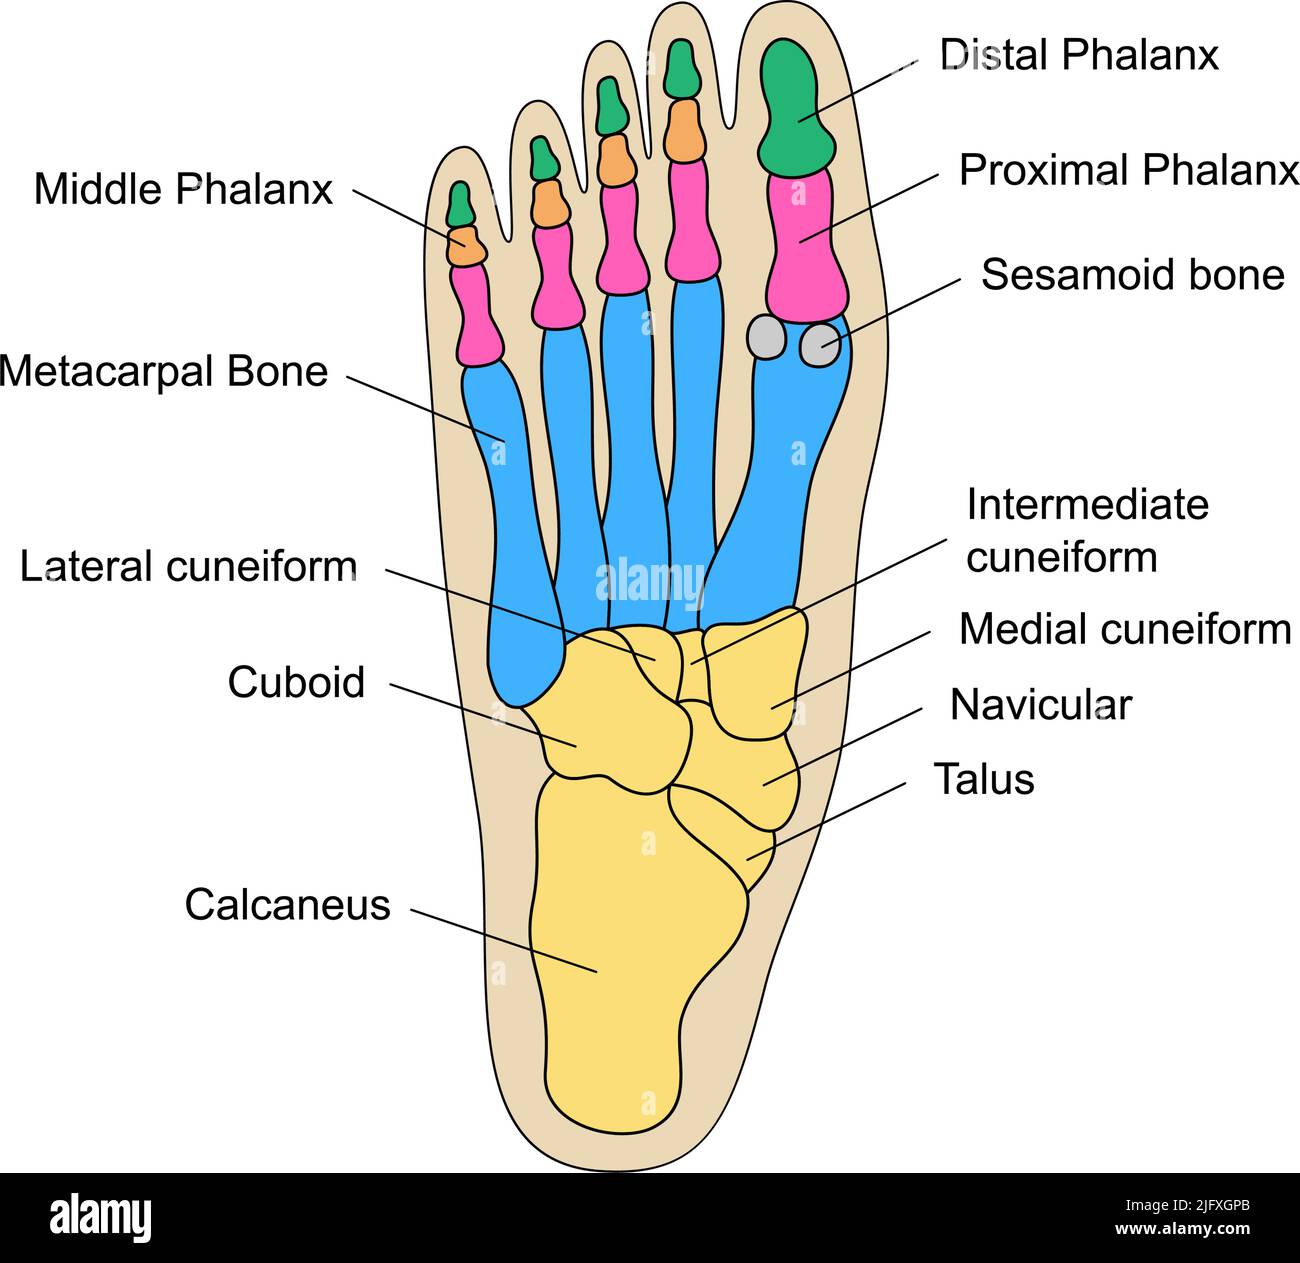

focusedcollection.comIllustrazione Su Anatomia Umana, Fondo Del Piede Illustrazione Di Stock

focusedcollection.comIllustrazione Su Anatomia Umana, Fondo Del Piede Illustrazione Di Stock

it.dreamstime.comanatomia umana piede

it.dreamstime.comanatomia umana piede

www.sanitariabresciana.comAnatomia Delle Ossa Del Piede Umano Con Descrizioni. Diagramma

www.sanitariabresciana.comAnatomia Delle Ossa Del Piede Umano Con Descrizioni. Diagramma